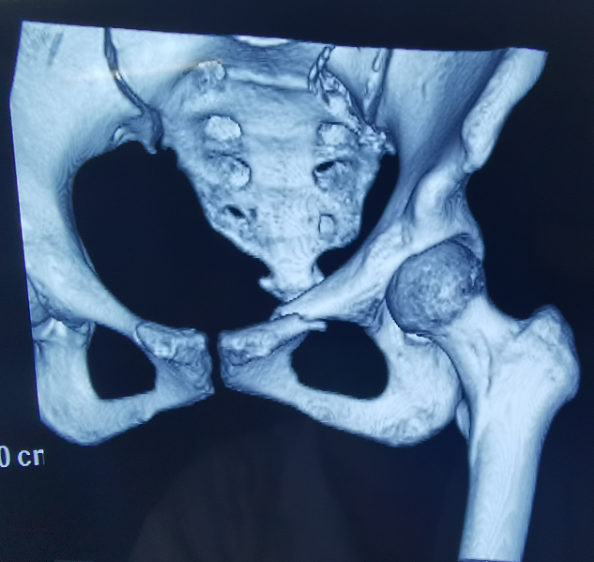

近日,天玑®骨科手术机器人落户南昌市第一医院,助力骨盆骨折闭合复位内固定术顺利完成。作为江西省首先采用5G引导下的骨科机器人手术,天玑®骨科手术机器人用它的“透视眼”,以三维影像扫描进行深层三维空间精准定位,为患者“量身定做”了最理想、最安全的教科书般通道,完成了复杂骨盆骨折微创治疗一次性完美置钉及腰椎骨折微创经皮置钉的首秀,成为江西省骨科发展的标志性事件,同时也是江西省骨科步入新型数字智慧骨科时代的重要里程碑事件。

患者为22岁年轻女性,因车祸致骨盆骨折。骨盆骨折是一种复杂的创伤,传统手术方式需要比较大的切口,而且骨盆内有大量复杂血管和神经,手术难度和风险极大,是很多骨科医生的禁区。

我国自主研发的天玑®骨科手术机器人,是针对骨骼硬组织的先进技术,已经获得国际认可,能够开展脊柱全节段 (颈椎、胸椎、腰椎、骶椎) 疾病、骨盆和四肢等骨折、骨肿瘤以及关节导航等手术。相比传统手术,机器人辅助手术具有手术创伤小、出血少、并发症少、康复快的优势。同时,由于不需通过反复透视来确定置钉位置,从而能减少术中辐射,大大降低患者辐射危害,且手术过程中,由机器人与主刀医师共同完成手术,大大增加了手术安全性。